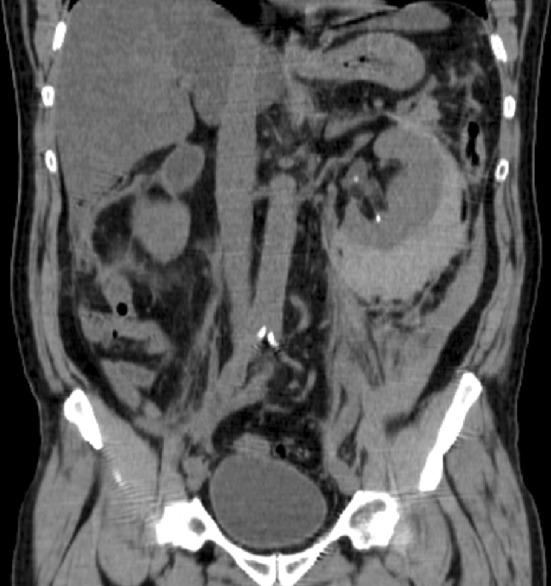

It is well recognized that the popularity of extracorporeal shock wave lithotripsy (SWL), despite its non-invasive character, has decreased during recent years. This is partly explained by the technological achievements in endoscopy and urologists' enthusiasm for such procedures. Another explanation is that many urologists have been insufficiently successful with SWL. The latter effect might to some extent be a result of the performance of the lithotripter used, but in too many cases, it is evident that the principles of how shock wave lithotripsy should be carried out are poorly applied. The purpose of this article is to emphasize some important aspects on how SWL best should be used. Based on decades of experience, it stands to reason that success with SWL does not come automatically and attention has to be paid to all details of this technique.